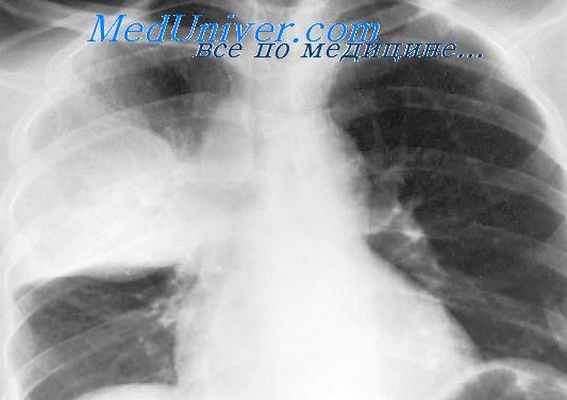

При аэрогенном заражении в легких первичный туберкулезный очаг (аффект) возникает субплеврально в наиболее хорошо аэрируемых сегментах, чаще правого легкого - III, VIII, IX, X (особенно часто в III). Он представлен фокусом экссудативного воспаления, причем экссудат быстро подвергается некрозу. Образуется очаг казеозной пневмонии, окруженный зоной перифокального воспаления. Размеры аффекта различны: иногда это альвеолит, едва различимый микроскопически, но чаще воспаление охватывает ацинус или дольку, реже - сегмент и в очень редких случаях - всю долю. В казеозных массах первичного аффекта длительное время сохраняются эластические и аргирофильные волокна каркаса легкого.

Постоянно наблюдается вовлечение в воспалительный процесс плевры с развитием фибринозного или серозно-фибринозного плеврита.

Очень быстро специфический воспалительный процесс распространяется на прилежащие к первичному очагу лимфатические сосуды - развивается туберкулезный лимфангит. Он представлен лимфостазом и формированием по ходу лимфатических сосудов в периваскулярной отечной ткани туберкулезных бугорков. Образуется как бы дорожка от первичного очага к прикорневым лимфатическим узлам.

В дальнейшем воспалительный процесс довольно быстро переходит на регионарные бронхопульмональные, бронхиальные и бифуркационные лимфатические узлы, в которых развивается специфический воспалительный процесс с быстро наступающим казеозным некрозом. Возникает тотальный казеозный туберкулезный лимфаденит. Лимфатические узлы увеличиваются в несколько раз и на разрезе представлены казеозными массами. Изменения в регионарных лимфатических узлах всегда более значительны по сравнению с первичным аффектом.